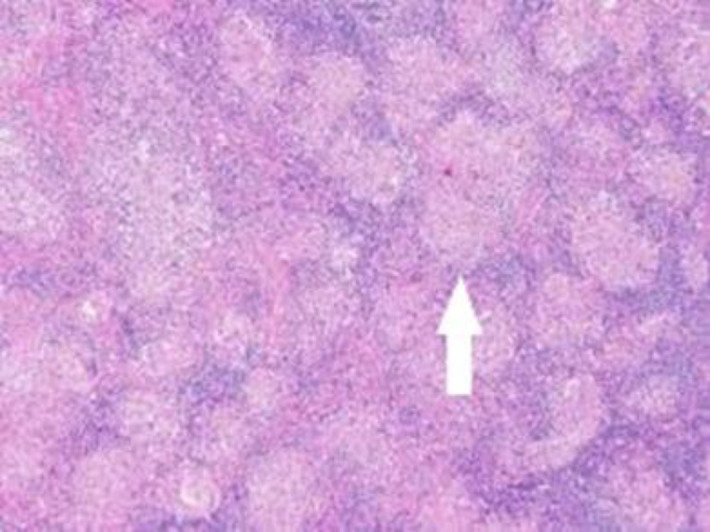

Gastrointestinal sarcoidosis mimicking malignancy: A confusing scenario.